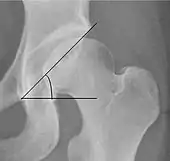

| Center-edge angle of Wiberg | ![]() |

The superior-lateral coverage of the femoral head. | |

| Tönnis angle | ![]() |

Slope of the sourcil (the sclerotic weight-bearing portion of the acetabulum) | 0 to 10°

|